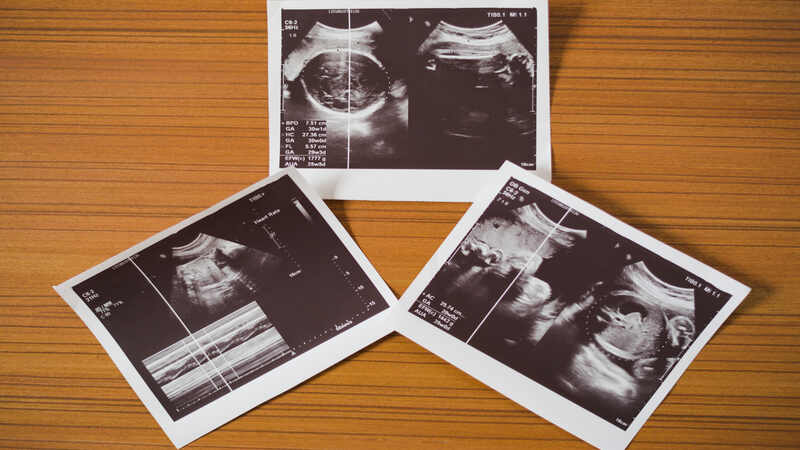

How to Read an Pregnancy Ultrasound Report?

1. Look at your womb

While performing the ultrasound or for the new parents when the doctor gives the picture of the ultrasound location of the womb, which means where the baby is present needs to be identified. The white or gray lines in the scan are the uterus inside which the black-colored sac-like structure is seen, that is the amniotic fluid where the small baby is present. But again the image can change the position of the baby according to the placement of the probe by the doctor.

2. Look at your baby

After identifying the womb, the next important structure to notice is the baby, which can be seen as a white or grayish image. The size of the baby can vary according to the gestation of the pregnancy. They are:

- Early gestation till around 8 to 10 weeks, the baby or the fetus can be seen as a lemon seed or bean.

- Following 12 weeks to 20 weeks of gestation the baby can be seen with a small head, spine, hands, and leg.

- Following 20 weeks till delivery, the baby can be visualized properly with proper face, eyes, nose, spine, hands, and legs.